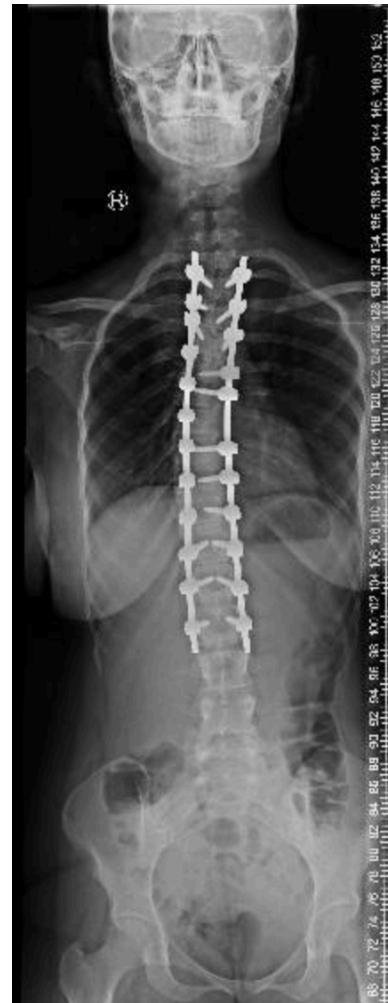

Scoliosis

Deformities

Scoliosis Classification

Adolescent Idiopathic Scoliosis

- Definition: Coronal plane spinal deformity most commonly presenting in adolescent girls from ages 10 to 18

Imaging:

Severity Grades:

- Mild: 10-25°

- Moderate: 25-45°

- Severe: >45°

Treatment Based on Severity:

- Observation: Mild curves, depending on age and skeletal maturity

- Bracing: Moderate curves (25-45°) in growing patients

- Surgery: Severe curves (>45°) or progressive curves